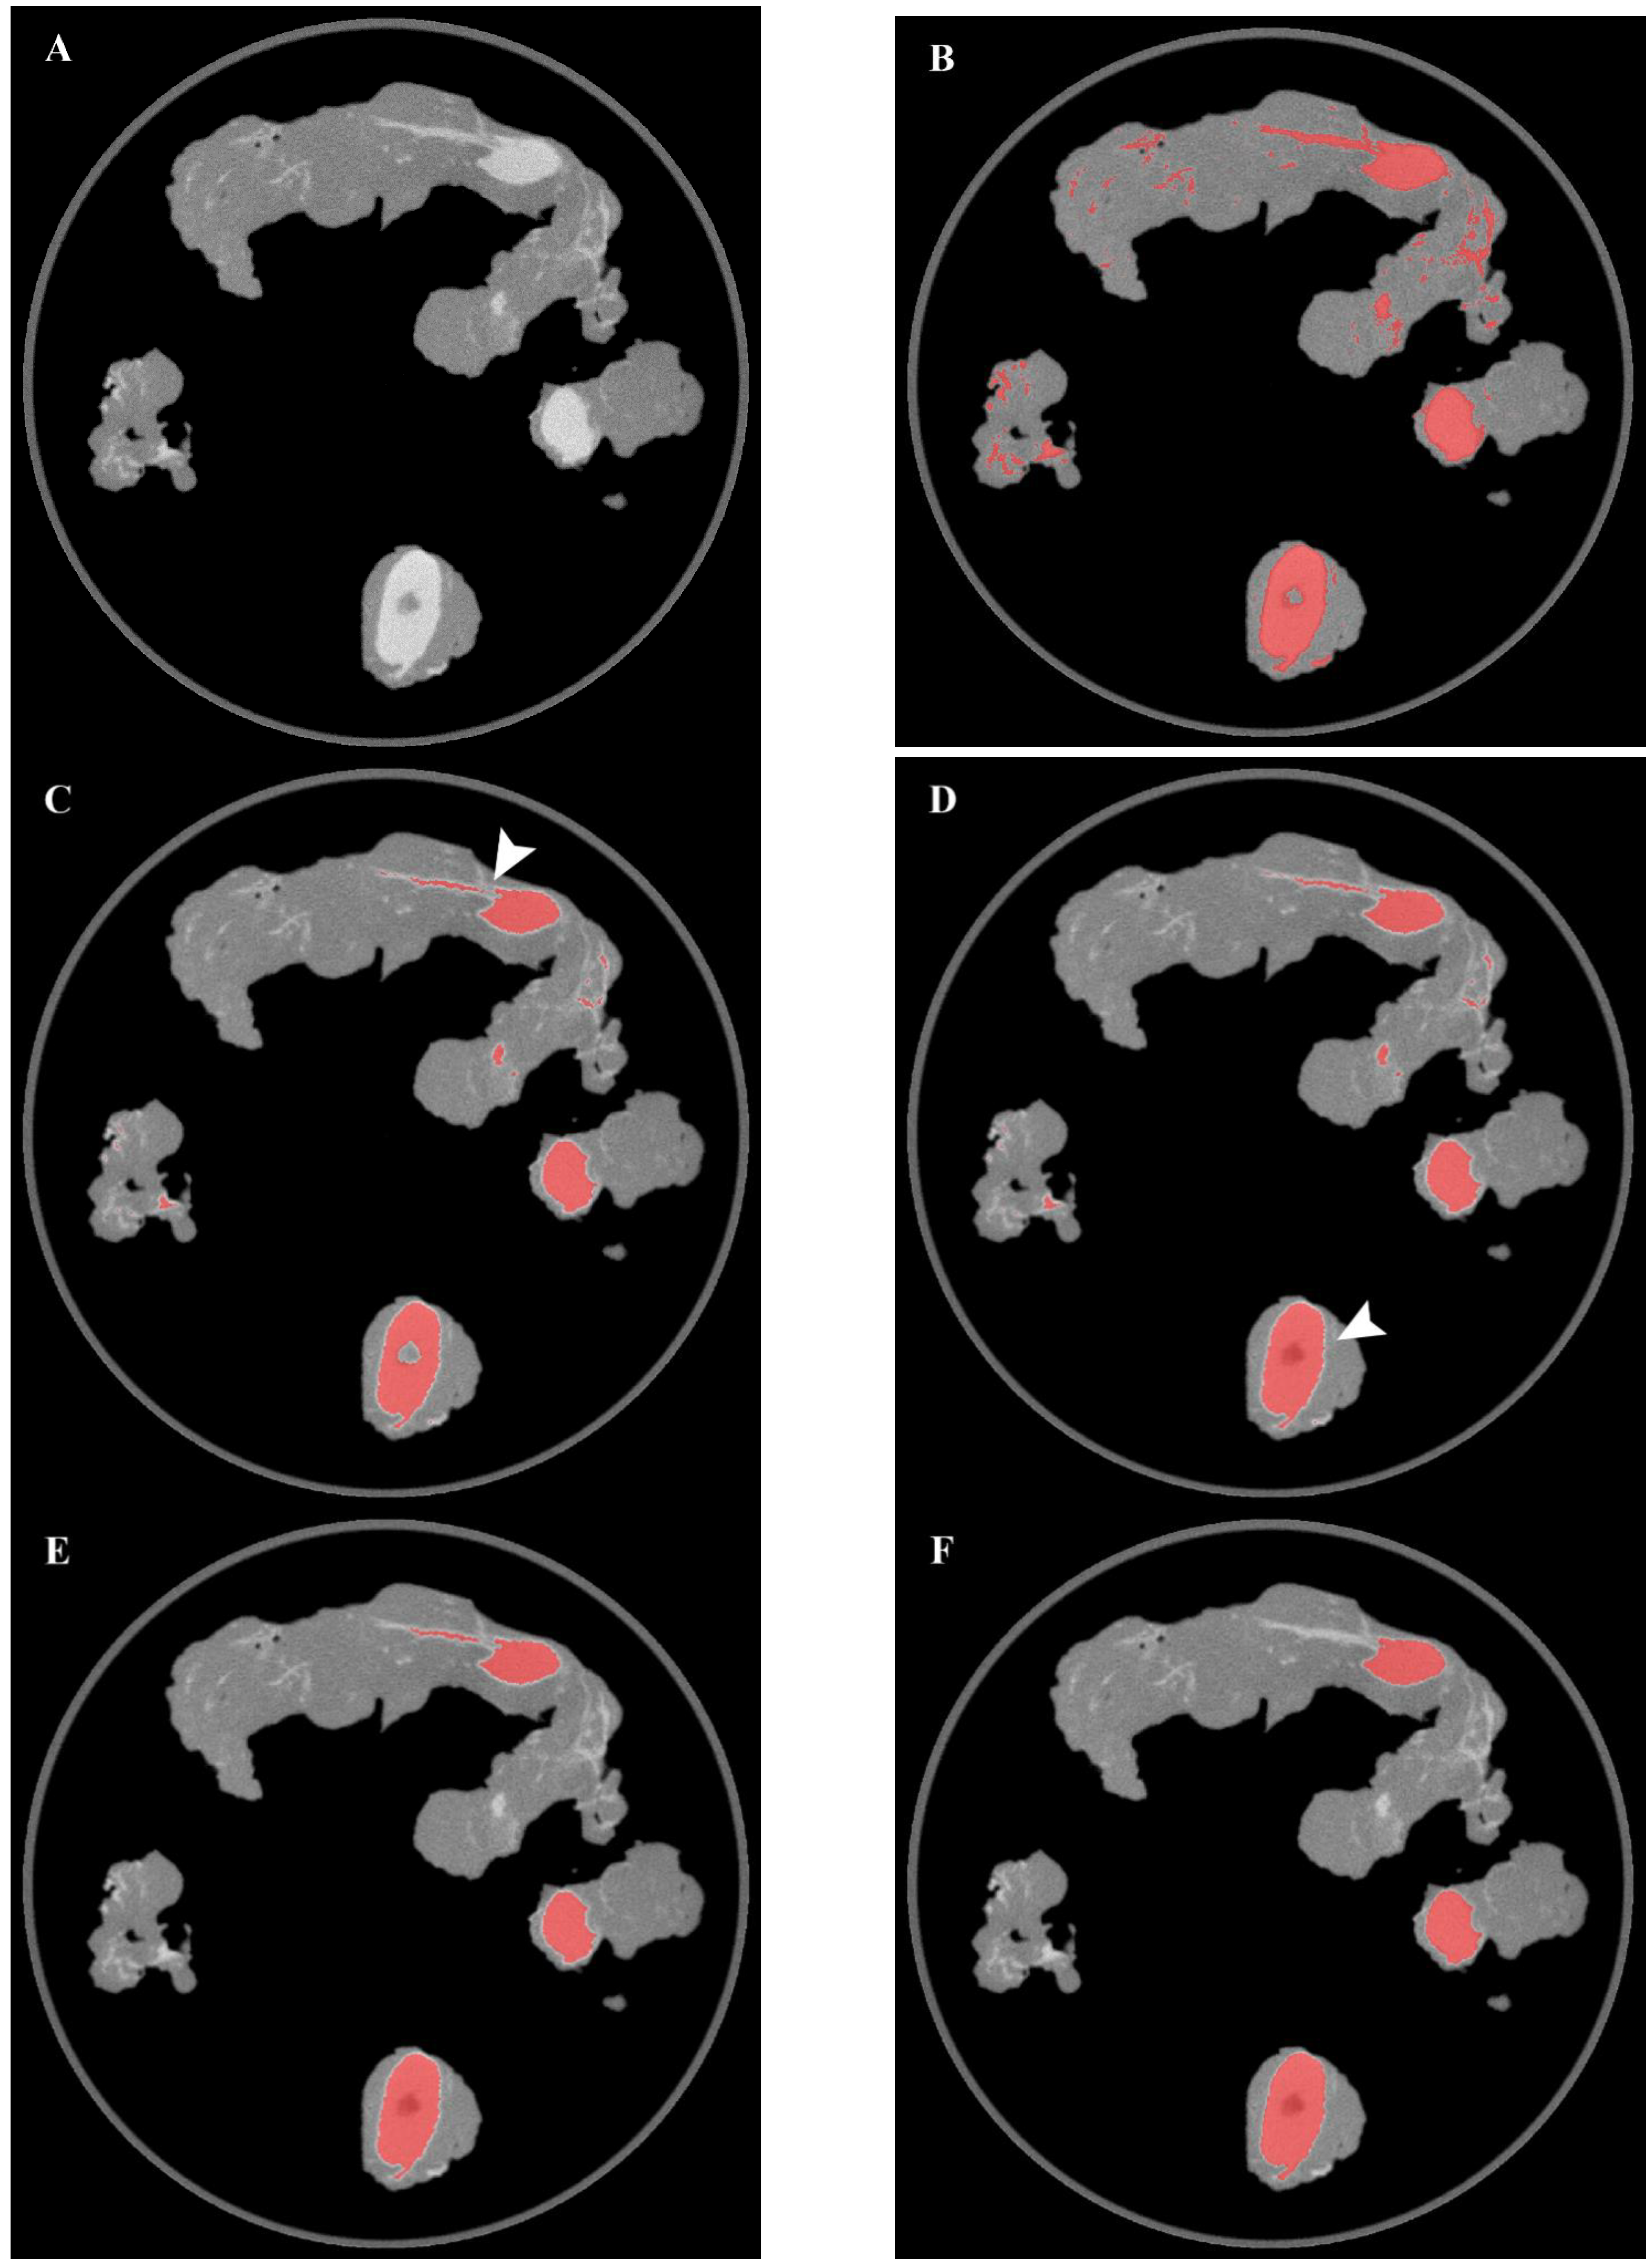

First, leveraging the difference in tissue density between the lymph nodes and the surrounding structures, a k-means clustering algorithm (n = 3 clusters) was applied to one-dimensional CT attenuation data to identify nodal structures. The model was initialized with three clusters, thus allowing to discriminate between air, fat tissue, and lymph nodes, plus adjacent vessels/fibrotic tissue. Considering the one-dimensional data and the clusters number, the use of the default random starting points did not affect the results. The cluster corresponding to the fat tissue was then removed by assigning to its elements the same value of the background (air), thus creating a binary two-level mask of the nodal cluster. The specimen case was also removed from the images using a filter based on geometric distance in order to prevent background noise due to misclassification errors. Then, morphological operations of erosion and hole-filling were performed. The erosion process allowed not only to reduce image noise but also to detach wrongly connected objects such as vessels or fibrous tissues located in close proximity to a nodal structure. On the other hand, the filling operations also extended the segmented areas to regions with lower densities—such as the lymph node hilum—which would otherwise be excluded from clustering. Examples of the results of the morphological operations (erosion/filling) are presented in Figure 2. Noise removal was then performed on 2D slices by discarding features with a low number of elements. Then, morphological dilation was applied to compensate for the previous erosion process and also to join broken parts of the same elements. Finally, further noise removal was performed on the 3D image by discarding features with a lower volume. An overview of the results of the main segmentation steps on a sample axial image is shown in Figure 2.

Figure 2. Overview of the results of the main segmentation steps on a sample axial image. (A) original CT image, (B) K-means clustering, (C) Erosion, (D) Filling, (E) 2D noise removal, (F) 3D noise removal. The erosion process allowed to detach two wrongly connected objects (arrow in panel (C)), while the hole-filling operation allowed to include the lymph node hilum in the segmented area (arrow in panel (D)).